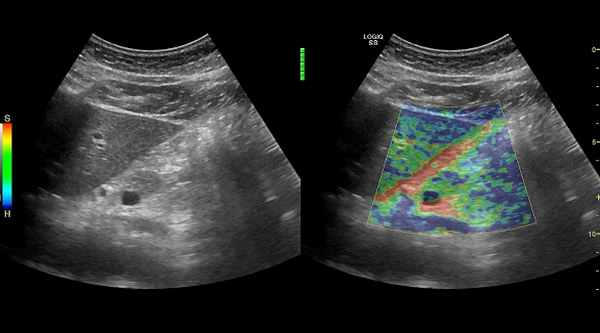

- УЗИ брюшной полости. Оцениваются признаки воспаления ткани поджелудочной железы, наличия камней в протоках, кальцинатов, кист, опухолей железы. Дополнительно определяются изменения со стороны других органов желудочно-кишечного тракта для исключения осложнений заболевания, а так же сопутствующей патологии.

УЗИ с эластографией здоровой поджелудочной железы